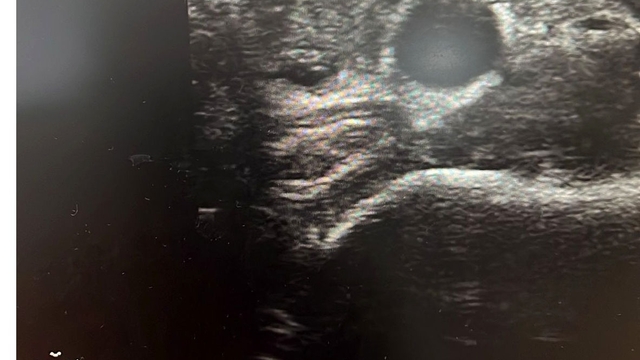

Tiroit nodülü tespitinde farkındalığın artığını ifade eden Dr. Demir, "Nodül tespitindeki farkındalığımız arttı. Tiroit ultrasonu kullanıyor olmamız da bu artışa etken oldu. 'Bası bulgusu' ile dokunarak muayene ettiğimizde; mevcut olan nodüllerin yaklaşık yüzde 20’sini tespit edebiliyoruz. Nodüllerin birçoğunun özelliklerini ve boyutlarını ise tiroit ultrasonu ile tespit ediyoruz. Son dönemlerde vakalarda artış var. Bazen hiçbir semptomu olmayan hastalarda da tiroit nodülleri tespit ediyoruz. Nodülleri özelliklerine göre değerlendirerek gerekli hastalardan biyopsi alıyoruz. İyi ya kötü huylu nodüle göre tedavi uyguluyoruz. Nodülü belli aralıklarla takip ediyoruz. Tiroit nodüllerinin yüzde 10 ila 20 kadarı kötü huylu olabiliyor. Birçok kanser türü erkek hastalarda fazla görülürken, özellikle tiroit kanseri sıklığı kadın hastalarımızda daha yüksektir. Kadın hastalar daha sık muayeneye geliyor ve farkındalıkları daha yüksek" diye konuştu.